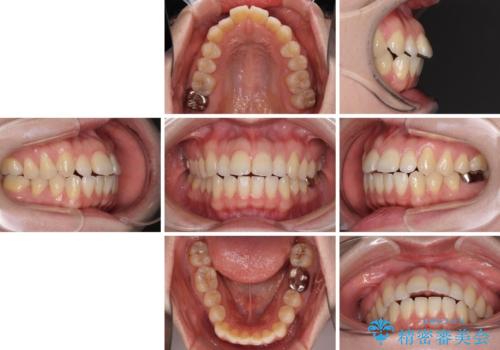

- 唇の閉じにくさを気にして来院された患者様です。

上下左右第一小臼歯4本を抜歯し、ワイヤー装置にて口元を引っ込めるよう矯正治療を行うこととしました。

骨格的に下顎がやや前方にあるため、横顔のシルエットが著しく変化することはありませんでしたが、口元はスッキリと引っ込み、唇が閉じやすくなりました。